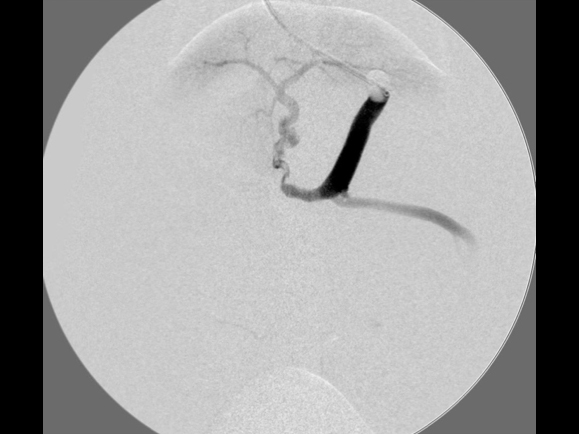

門脈造影検査